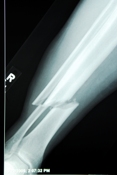

Radiographers, also known as radiologic technologists, are medical personnel who perform diagnostic imaging examinations, accurately position patients, ensure quality diagnostic images are produced, and adhere to radiation protection regulations for themselves, their patients, and coworkers. They work closely with radiologists, the physicians who interpret medical images, to diagnose or rule out disease or injury.

Most radiographers or radiologic technologists work in hospitals, physicians' offices and clinics, or diagnostic imaging centers. Multi-skilled RT(R)s who are educated and credentialed in more than one type of imaging technique are the most marketable. With experience and additional education, staff radiographers may become specialists, performing CT, mammography, angiography, and magnetic resonance imaging, or advance into management or education. Radiation therapy, sonography, and nuclear medicine typically require an additional specialty training program. Currently there are job openings throughout the country. Salaries are competitive with other healthcare professions that require similar education. Mean annual earnings for radiographers is $56,760 (www.bls.gov, "National Occupational and Wage Estimates", May 2010)